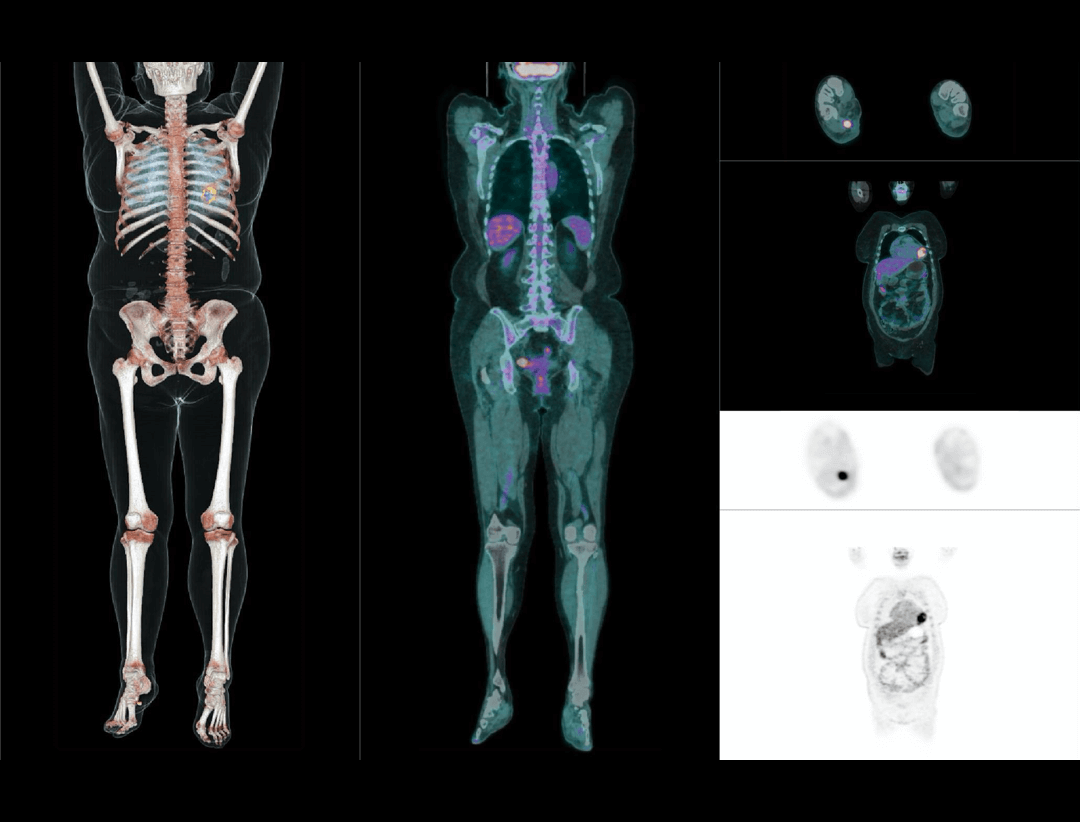

2.9mm

超清NEMA分辨率成像